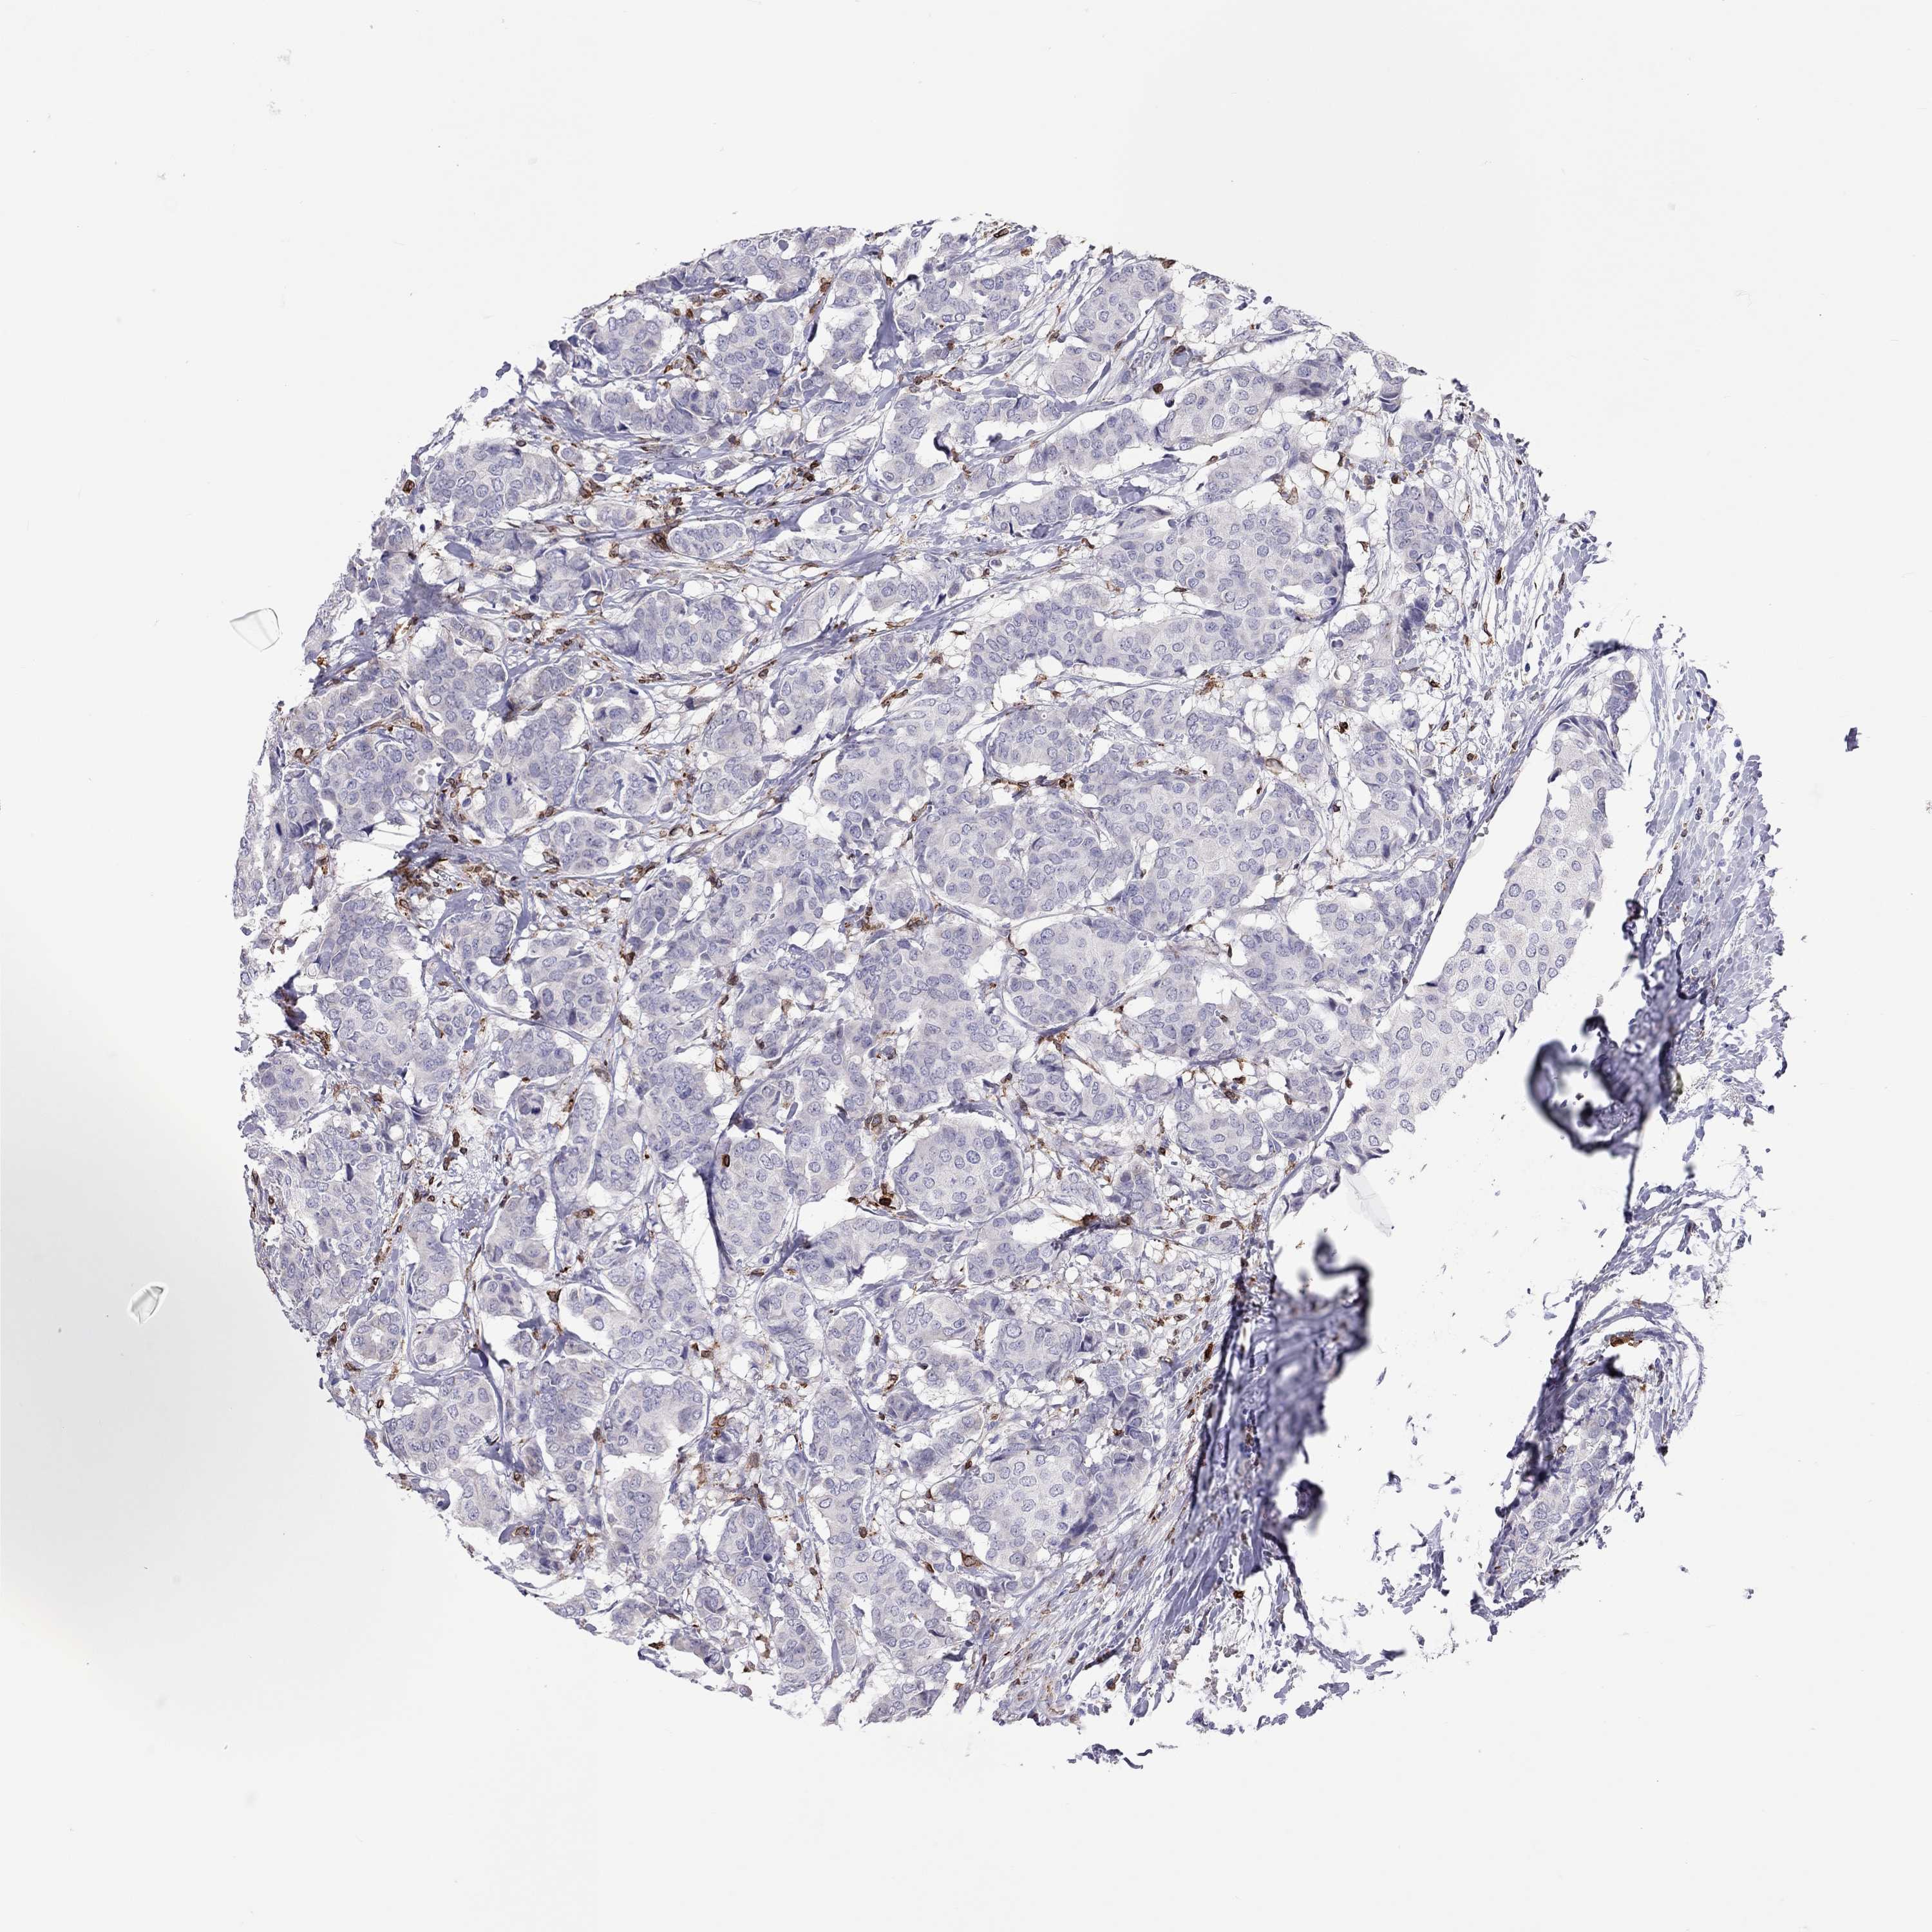

CANCER BREAST CANCER Show tissue menu

BRCA TCGA BRCA VALIDATION PROTEIN EXPRESSION